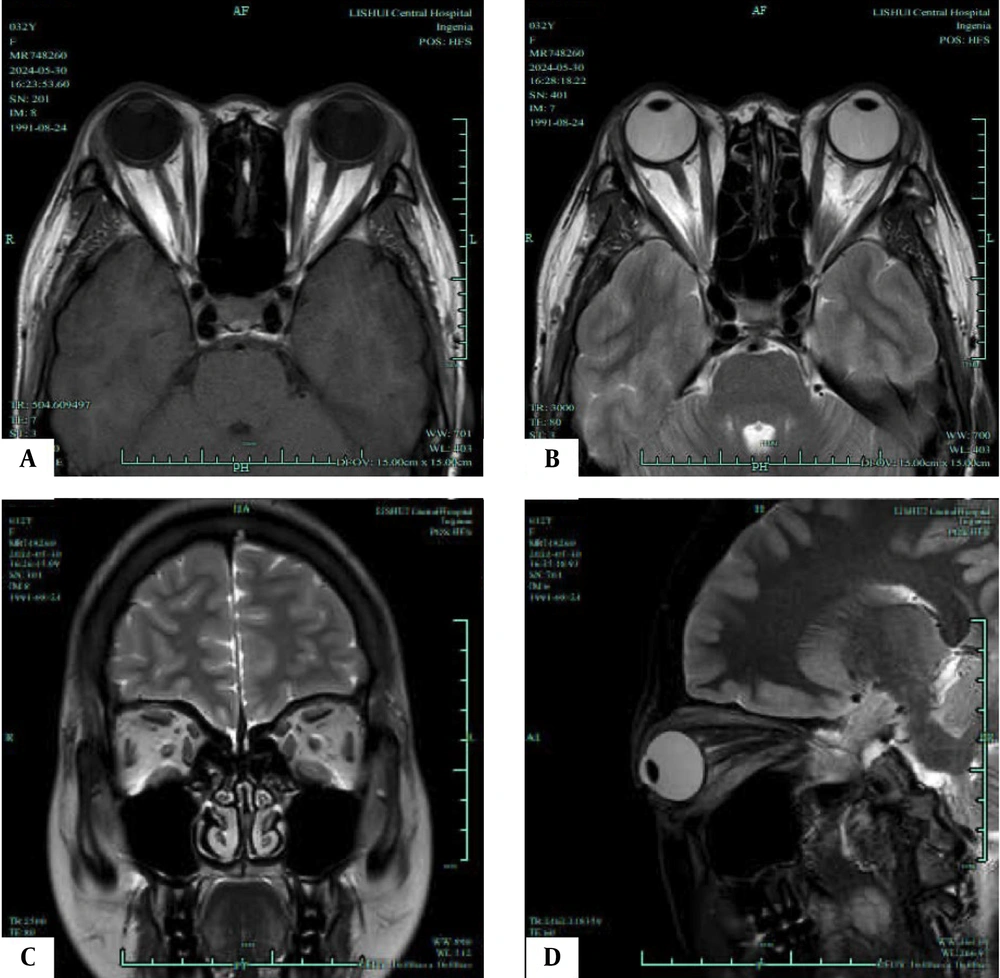

To evaluate the feasibility of Dixon and T2 localization for assessing disease severity and progression, this study examined the measurement parameters of both active and inactive groups, as illustrated in Figures 2 and 3. Tables 3 and 4 present the results. The active group demonstrated significantly higher average EOM water fraction (0.98 ± 0.25 vs. 0.80 ± 0.16), average EOM water signal intensity (398.96 ± 102.45 vs. 326.70 ± 80.46), average EOM fat signal intensity (96.32 ± 12.15 vs. 78.90 ± 10.48), average lacrimal gland signal intensity (79.52 ± 10.24 vs. 68.60 ± 10.12), average of unilateral four EOM fat fractions (67.20 ± 8.82 vs. 50.45 ± 7.60), average EOM T2 value (79.45 ± 7.42 vs. 75.60 ± 6.80), and average EOM cross-sectional area (50.48 ± 7.22 vs. 39.60 ± 6.40) compared to the inactive group. These differences were statistically significant (t = 3.883, 3.469, 6.715, 4.616, 8.899, 2.349, 6.952, P < 0.05).

T1/T2-weighted magnetic resonance imaging (MRI) of an inactive phase patient. A, Axial T1-weighted MRI shows the most distinct visualization of the enlarged extraocular muscles (EOMs) during the inactive phase; B, Axial T2-weighted MRI highlights the same EOMs; C, Coronal T2-weighted MRI shows the most distinct visualization of the enlarged EOMs during the progression phase; D, Sagittal T2-weighted MRI highlights the same EOMs.